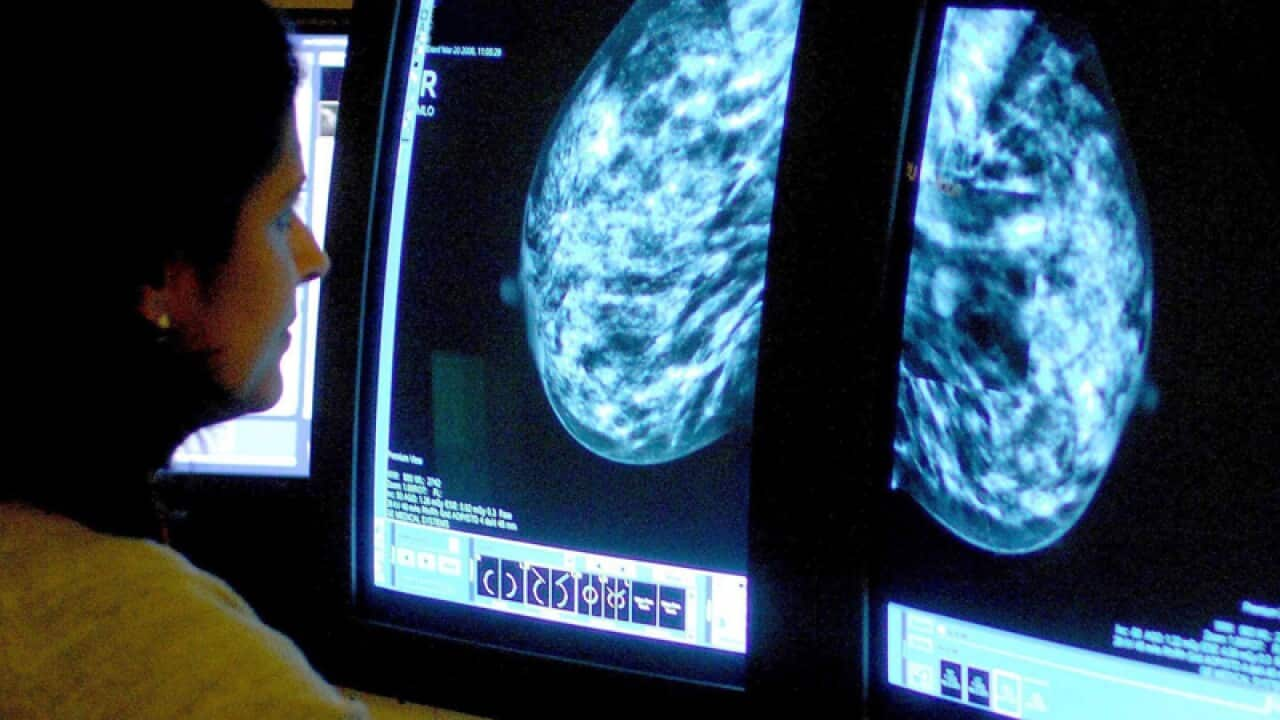

Australians using menopausal hormone therapy (MHT) are twice as likely to develop breast cancer than those who have never used it, says new research.

The research analysed data from 1236 postmenopausal Australian women with breast cancer and 862 who did not have the disease.

Other breast cancer risks, such as family history, were also taken into account to conclude women currently using MHT were twice as likely to develop the disease.